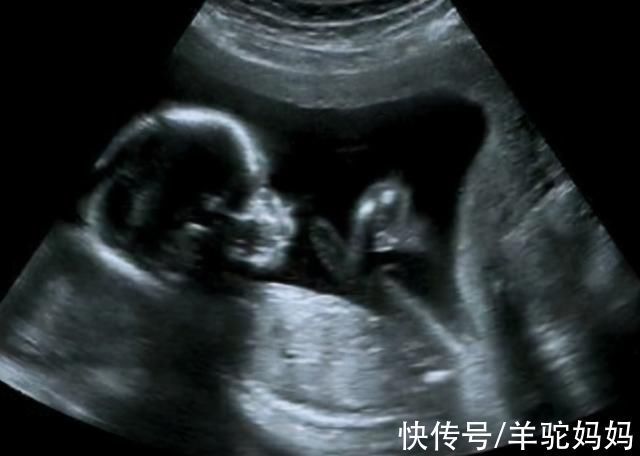

看胎心数据,辨别胎儿性别

有人说女宝宝的胎心跳会比较快,而男宝宝的跳比较慢,那么就有人表示,胎心在每分钟140次以上的就是为女孩,胎心在140以下的就是男孩,这是非常错误的想法。

因为在分娩时,女孩的心率的确是会比男孩的心率更快,但是在增长过程中和发育过程中,胎儿的心率是会随之变化的,并不能是固定的,所以通过这个来辨别男女,这是并不可靠。